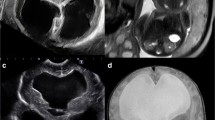

Fetal magnetic resonance imaging (MRI), as shown in Fig. 2, is increasingly used to improve the diagnosis of structural abnormalities suspected on US. Fetal MRI is especially useful for detecting small foci of brain hemorrhage, depicting corpus callosum anomalies, and assessing cortical development [23]. Furthermore, certain abnormalities, such as cortical malformations, porencephaly, migrational abnormalities, and white matter pathologies may be better detected on fetal MRI than US. Unlike US, MRI allows for complete visualization of the ventricles and brain parenchyma without artifacts from surrounding skull ossification or fetal position [24] (Fig. 3). The major limitations of fetal MRI are poor image quality due to fetal motion, cost, and availability [23]. Fetal brain MRI is usually performed at 20 to 24 weeks of gestation, as developmental milestones are more evident at these times and discontinuation of pregnancy may still be an option [8].

There remains debate on the additive benefit of fetal brain MRI when US shows no abnormalities, especially in cases of mild or moderate VM, and rates of additional findings by fetal MRI vary [23, 25]. In a prospective study of 59 fetuses, additional findings by fetal MRI were found in 17% of cases [18]. Although categorical assessments of ventricular size by fetal MRI were concordant with US in 90% of cases, other abnormalities were revealed in 25 of 147 fetuses (17%) [7]. When looking specifically at the degree of VM, previously unidentified abnormalities were found in 5 of 90 patients (6%) with mild VM, 4 of 29 patients (14%) with moderate VM, and 16 of 28 patients (57%) with severe VM [7]. Of note, the likelihood of finding an abnormality on MRI and not on US depends, in part, on the quality of the US examination and varies overall from 5 to 50% in other studies [26,27,28,29]. Agenesis of the corpus callosum was the most common anomaly to be detected by MRI but missed on US [7]. However, in moderate or severe VM, the enlarged ventricles may obscure the corpus callosum, whereas color Doppler may be used on US to look for the pericallosal artery to confirm partial or complete corpus callosum absence. Some groups recommend fetal MRI in all cases of isolated ventriculomegaly [8]. Also, it is important to note that the absolute value of AD may differ on US and MRI.

Fetal MRI of aqueductal stenosis. Axial (a), sagittal (b), and coronal (c) images were obtained by half-Fourier acquisition single-shot turbo spin-echo fetal MRI at 35 weeks and show severe ventriculomegaly (atrial diameter > 15 mm). Preferential enlargement of the occipital horns and the third ventricle with a normal-sized fourth ventricle indicate aqueductal stenosis